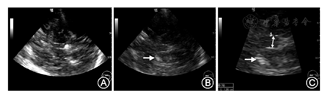

(1)声窗条件评估:TCS检查是经过颞骨的声窗完成,声窗条件好坏对检查能否成功至关重要,因此,首先评价声窗情况。声窗条件分为声窗良好、声窗欠佳和透声不良3种情况(图3)。

(2)TCS检查包括脑的四个平面:中脑平面、第三脑室丘脑平面、侧脑室平面和后颅凹小脑平面(图4)。检测内容包括中脑黑质、基底节区及小脑有无异常回声信号、中缝核是否连续完整、测量第三脑室宽度、侧脑室宽度。如果发现中脑黑质有异常高回声信号,评估回声强度并测量高回声的面积。

①中脑层面:此层面的标志是相对均匀的蝴蝶形的中脑低回声区被周围高回声的基底池所环绕(图5)。在低回声的中脑内可看到红核的回声,中线部位的高回声信号为脑干中缝和导水管。观察中脑黑质区有无异常高回声,如发现与正常相比扩大的黑质区高回声信号,冻结图像,回放找到最清楚的部位。半定量评估回声强度并将图像放大2~3倍后测量高回声信号的面积。

中脑黑质回声强度的半定量评估标准[17,18,19]:Ⅰ 级:黑质的回声强度与脑干相同;Ⅱ 级:黑质区有清晰可见的回声但强度仅稍高于脑干;Ⅲ级:中等回声强度,但低于周围脑池(图6);Ⅳ级:和周围脑池有相同的回声强度;Ⅴ 级:回声强度高于周围脑池。

中脑黑质的回声>Ⅱ级并且≥0.20 cm2视为异常。

在中脑平面还可以观察到脑干中缝核回声信号是否连续,正常时中缝核高回声信号为一条连续的线,中断或无回声提示异常,异常者需要从双侧颞窗扫描确认。

中缝核分级:1级:中缝核回声中断或无回声;2级:中缝核为高回声连续线。

②第三脑室、丘脑平面:将探头从中脑平面向上倾斜大约10°为第三脑室平面,此层面可以看到两条平行的第三脑室回声信号、基底节区和丘脑(图7A)。测量第三脑室宽度,观察双侧基底节区豆状核、尾状核、丘脑有无异常高回声信号(图7B,图7C)。第三脑室最大横径:20~60岁<7 mm,≥60岁<10 mm。

③侧脑室平面:将探头从中脑平面向上倾斜大约25°是侧脑室平面(图8)。此平面可观察侧脑室宽度,测量侧脑室额角距离:20~60岁<17 mm,≥60岁<20 mm。

④后颅凹小脑平面:探头从中脑平面向背侧旋转45°并向小脑方向倾斜10~15°为后颅凹小脑层面(图9)。此平面观察小脑齿状核有无异常回声信号,第四脑室有无异常扩大。